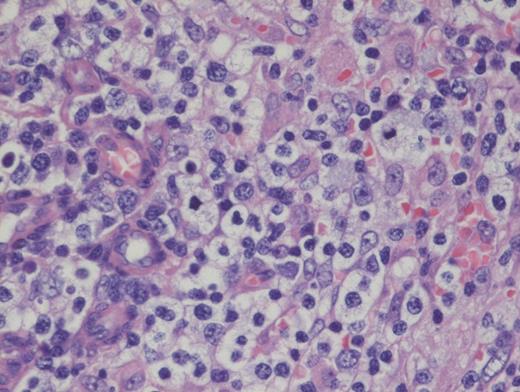

Hematoxylin and Eosin Stain Showing Architectural Effacement by a Proliferation of Medium-sized Mononuclear Cells. Alternate view of hematoxylin and eosin stain depicting architectural effacement by this proliferation of medium sized mononuclear cells.

Angioimmunoblastic T-cell lymphoma (AITL) is histologically identified by T-cells having ample clear cytoplasm in a background of prominent vasculature and a mixed inflammatory microenvironment (plasma cells, histiocytes, and immunoblasts). The process effaces the typical nodal architecture with retraction of the peripheral cortical sinuses, in addition to numerous new follicular dendritic meshworks outside of the follicles in the perivenular regions. There are numerous associated reactive B-lineage immunoblasts in the background in addition to the neoplastic T-cells.1 This specific case was positive for CD3 and CD4 on the clear cells.

Nearly all cases of AITL have EBV-infected B cells in the background that may proliferate unchecked due to the local immunodeficiency caused by AITL, or it may be a potential instigating factor, which, through antigen presentation, drives the T-cells to proliferate. It is important to note that the neoplastic T-cells themselves are not infected with EBV. These background EBV+ B-cells can transform into a second lymphoma such as diffuse large B-cell lymphoma,2 and hence, the astute hematopathologist must remain vigilant to identify such concurrent B cell lymphoproliferations within AITL, which may benefit from addition of anti-CD20 therapy.